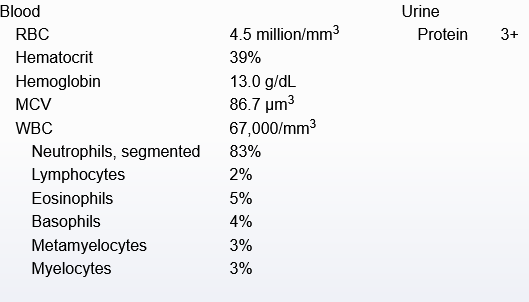

hypersensitivity pneumonitis

chronic myeloid leukemia

hypersensitvity pneumonitis - cause, features, dx, tx

inhalation of env/occupational antigens, usually animal (birds), fungi, bacteria, or inorganic chemicals leading to interstitual lung disease

acute - constitutional, flu-like sx, leukocytosisl; or more chronic - cough, dyspnea, fatigue, weight loss

diagnosed via hx & ct of chest showing fibrosis. also lymphocytosis on bronchoaleolar lavage, noncaseating granulomas on histopathology

avoid antigen, usually resolves spontaneously. can give glucocorticoids if symptoms persist. if refractory, may eventually require lung transplant